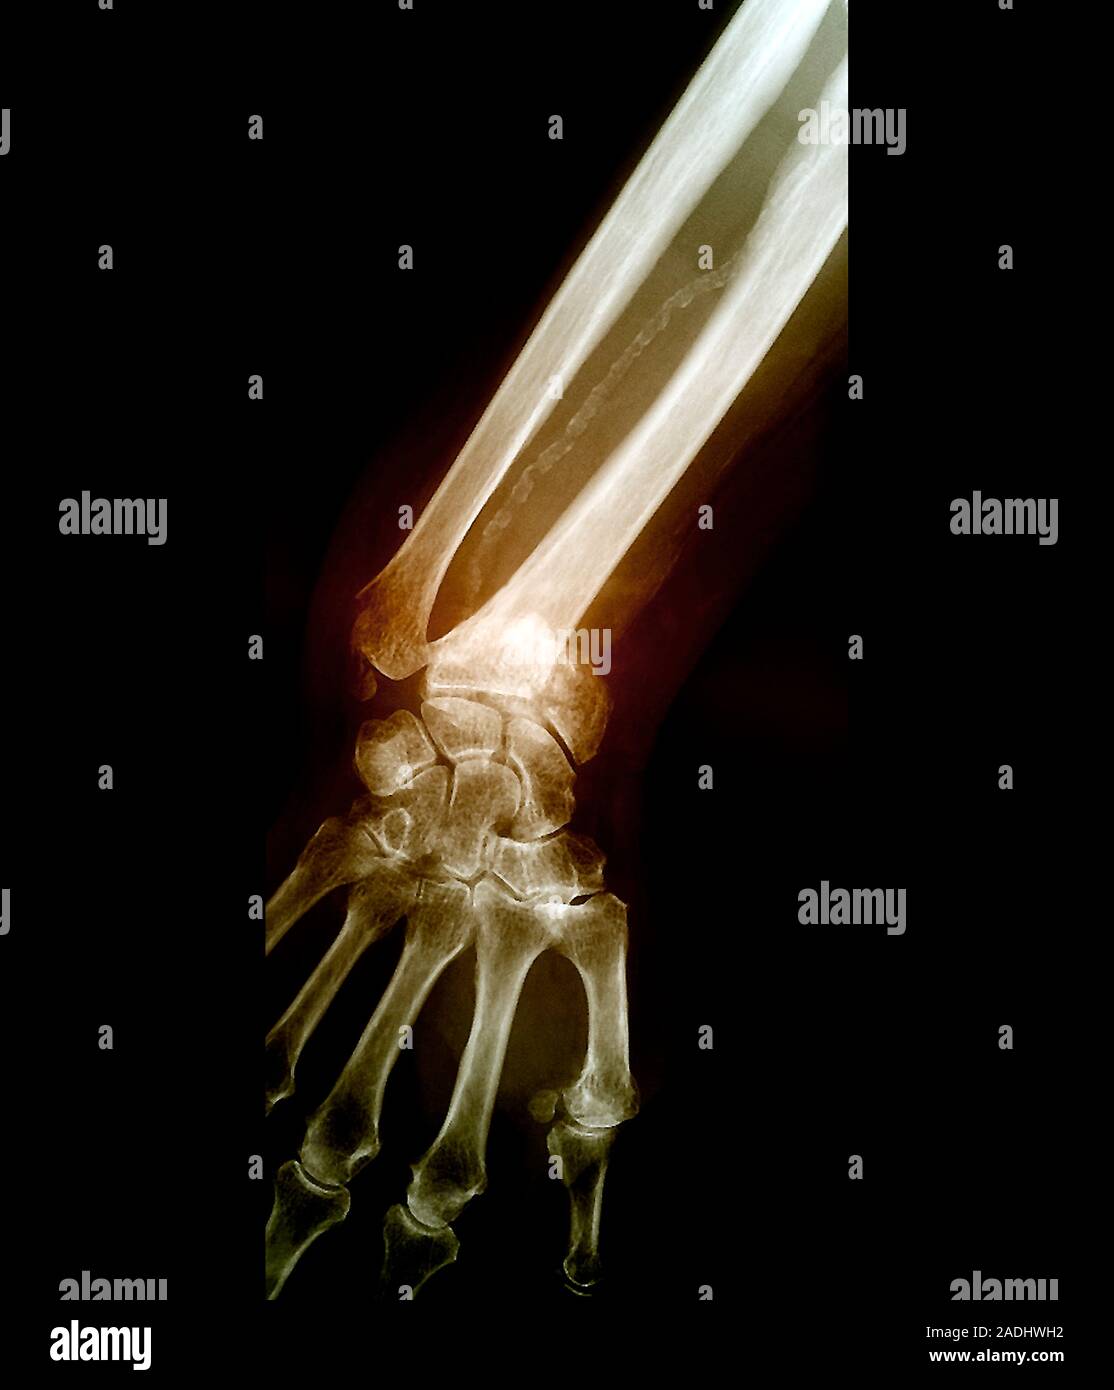

Colles' wrist fracture. Coloured frontal Xray of the hand and wrist

Colles Fracture X Ray Description . A fracture involving the articular surface with dorsal displacement of the wrist bones can be referred to as a barton's fracture. The colles' fracture is a break of the radius bone close to the wrist that results in an upward displacement of the bone. The colles fracture is defined as a distal radius fracture with dorsal comminution, dorsal angulation, dorsal. Normal radius length, normal radial. Some may call this a type of colle's fracture. High degree of comminution of the distal radius and a displaced fracture of the ulnar styloid. It is typically caused by falling on an outstretched.